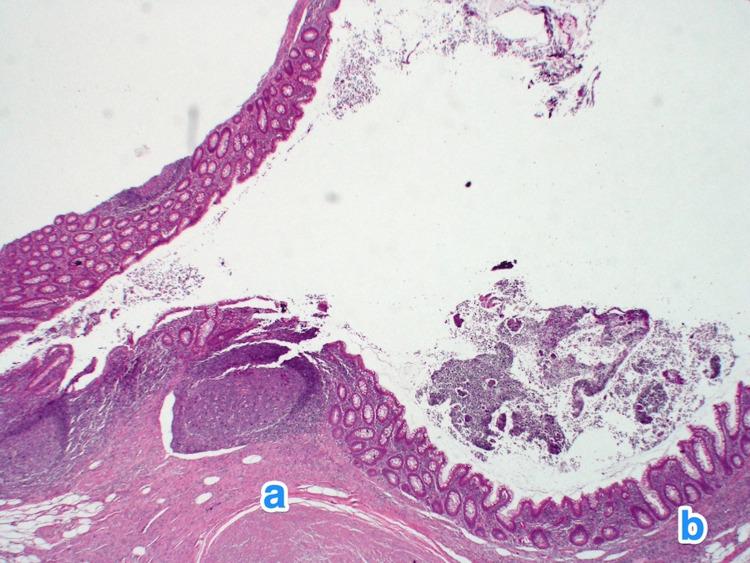

Appendicular diverticulitis (AD) is a rare entity characterized by the inflammation of the arising diverticulum of the appendix. It has been reported to carry a high risk of perioperative complications, such as bleeding and perforation. Furthermore, multiple articles have highlighted the importance of diagnosing AD early due to its strong association with malignancies. Limited published cases concerning AD in our country and globally are available in the literature. Hence, we present in this article a case series of five exciting cases of incidental findings of AD that were initially diagnosed as acute appendicitis based on clinical evaluation and imaging findings. In our series, we performed a retrograde evaluation of the computed tomography scans of all five cases that showed diverticula. In conclusion, histopathological evaluation remains the method of choice to reach the definitive diagnosis; however, it is essential to highlight the relevance of imaging in diagnosing AD preoperatively in the early stages to reduce morbidity and mortality.